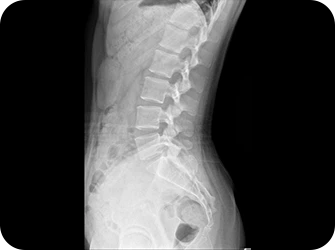

척추측만증 또는 좌, 우 한쪽으로 기울어진 척추로 인해 체중이 한쪽 허리로 집중된다면 장기적으로 체중이 기울어진 쪽 허리에 뼈가 자라거나 퇴행성 변화가 빠르게 진행됩니다.

목이 한쪽으로 기울거나 한쪽 어깨가 반대쪽에 비해 낮다면 상체의 무게가 한쪽 허리로 쏠리게 됩니다. 이때 낮은 쪽의 어깨는 광배근에 의해 허리로 연결되므로 어깨 높이 차이는 좌우 허리 근육의 불균형을 유발하여 허리 통증을 악화시킵니다.

허리는 골반위에 수직으로 서 있는 구조물이기 때문에 골반의 틀어짐은 필연적으로 허리를 틀어지게 만들어 허리에 많은 스트레스를 유발합니다. 만약 골반이 뒤로 기울어진 골반후방경사가 있다면 디스크탈출증을 더욱 악화시키며, 한쪽으로 회전되고 기울어진 골반은 체중이 집중되어 허리디스크와 협착증을 악화시키기 때문에 골반교정은 매우 중요합니다.

1. 평발은 요통의 위험을 약 4.5배까지 증가시킬 수 있습니다.

2. 요족은 발의 충격 흡수 능력을 저하시켜 보행 시 골반과 허리에 더 많은 스트레스를 줍니다.

3. 비대칭 족부 문제는 보행 패턴을 변화시키고 골반 비대칭을 유발하여 허리 통증을 악화시키는 주범입니다.

※ 허리 통증 치료 시 발의 상태를 함께 확인하고 교정하는 것이 매우 중요합니다. 발 교정을 통해 올바른 체중 분산과 보행 패턴을 만들어주면 허리 건강 개선에도 큰 도움이 됩니다.